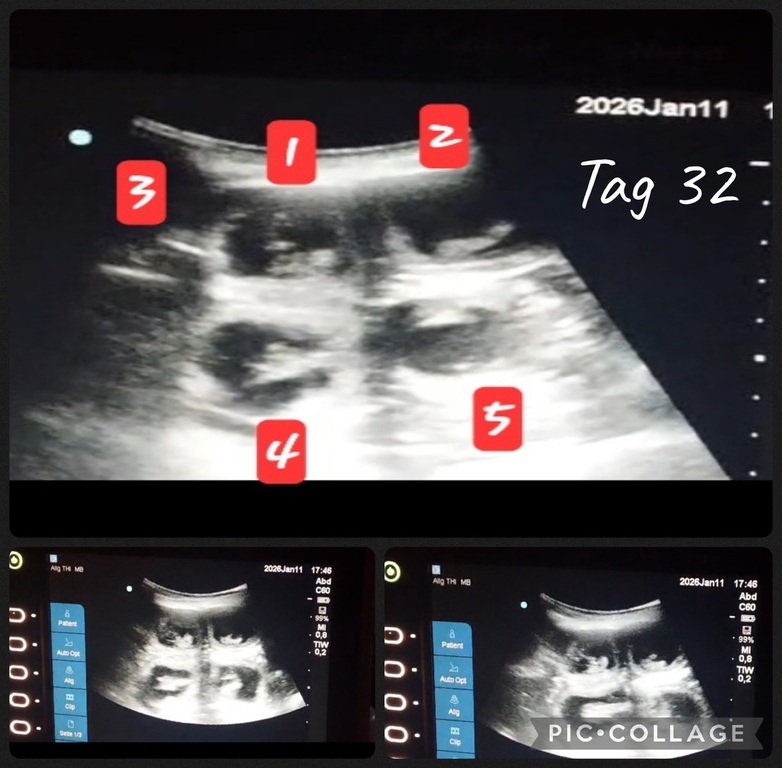

Fae ist trächtig und bekommt Mitte Februar ihren erste Wurf mit fast 3 Jahren. Fae hat vor einemb3/4 Jahr ein HUS und zwei Tage vor Belegung eine auskultation HG 0. Ihre Mutter ist die wundervolle Isabella Marie genannt 8 Jahre alt und in Rente seid 1,5 Jahren .Sie lebt bei uns . Mama Marie hat eine wundervolle Ahnentafel ,ihr Vater Faes Opa ist fast 15 Jahre alt geworden. Tolle alte Linien in der AT.

Seid Sonntag sind wir wieder glückliche Besitzer eines Ultraschallgerätes. Ein wunderbares leichtes und auch tragbares US. Durch liebe Menschen hatten wir glück dieses noch nicht so alte Ultraschallgerät zu bekommen. (War vor kurzem noch im Einsatz im KH Notaufnahme). Danke Pelin & Hanno